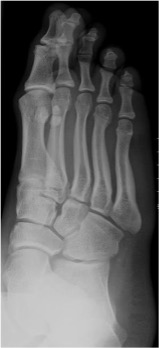

Dorsoplantar oblique view foot

Radiographic technique

A non-weightbearing view which may be taken in several ways. The most common method is for the patient to sit and incline the plantar surface of the foot 45° to the image receptor, with the X-ray beam directed to the base of the third metatarsal perpendicular to the dorsum of the foot.

Anatomical review areas

- Gives a distorted image of the midtarsal area but is particularly useful for the open view of the articular facets, particularly the talo-navicular, navicular-cuneiform and calcaneo-cuboid joints

- Anterior subtalar joint

- Tarso-metatarsal (Lisfranc) joints

- Difficult to see the facets of all the intercuneiform joints due to superimposition

- Good views of distal calcaneus, metatarsals, metatarsophalangeal joints and phalanges